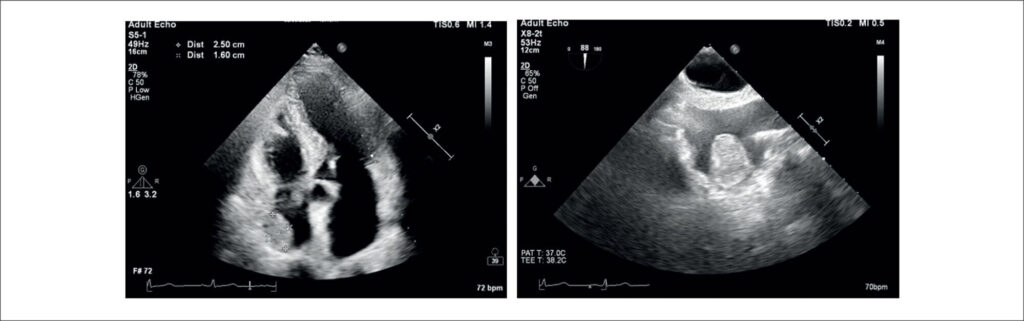

Lipoma Cardíaco como um Achado Incidental em Exame de Imagem Cardiovascular

O advento da imagem cardíaca inaugurou uma era em que achados incidentais podem ser detectados utilizando métodos menos invasivos, mesmo em pacientes assintomáticos. A apresentação clínica das massas cardíacas, caracterizadas pelas suas diferentes taxas de crescimento e diversas localizações dentro do coração, representa um desafio formidável para os cardiologistas. Portanto, é de suma importância a redução da carga clínica e dos custos, considerando o potencial da imagem cardíaca para otimizar o percurso clínico. As massas cardíacas mais comuns no átrio direito incluem trombos, vegetações e neoplasias. Aproximadamente 75% dos tumores primários são benignos, com mixomas compreendendo 50% dos casos benignos. Outros tumores benignos que geralmente podem surgir no átrio direito são rabdomiomas, fibromas, fibroelastomas e lipomas. Os lipomas cardíacos são raros, representando 2,9% a 8% de todos os tumores cardíacos benignos. Eles ocupam o terceiro lugar em frequência, depois dos mixomas e dos fibroelastomas papilares. A literatura sugere que 25% dos lipomas cardíacos são intramiocárdicos, 25% são extracavitários de origem epicárdica e 50% são intracavitários de origem subendocárdica. Lipomas são massas bem encapsuladas e homogêneas compostas por gordura madura. Embora a etiologia dos lipomas cardíacos seja desconhecida, eles podem originar-se de qualquer um dos três tecidos cardíacos: subendocárdico (o mais comum), pericárdico ou miocárdico.

O objetivo deste relato é apresentar um caso de lipoma atrial direito assintomático e discutir a etiologia, história natural e estratégias de manejo ideais para lipomas atriais direitos.